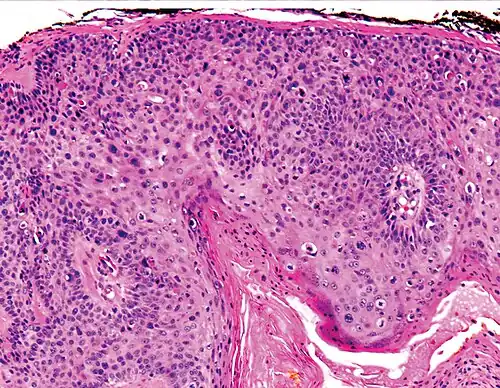

Histopathology of squamous-cell carcinoma in situ (black arrow), compared to normal skin, showing marked atypia. -

Squamous-cell carcinoma in situ, showing prominent dyskeratosis and aberrant mitoses at all levels of the epidermis, along with marked parakeratosis.[12]